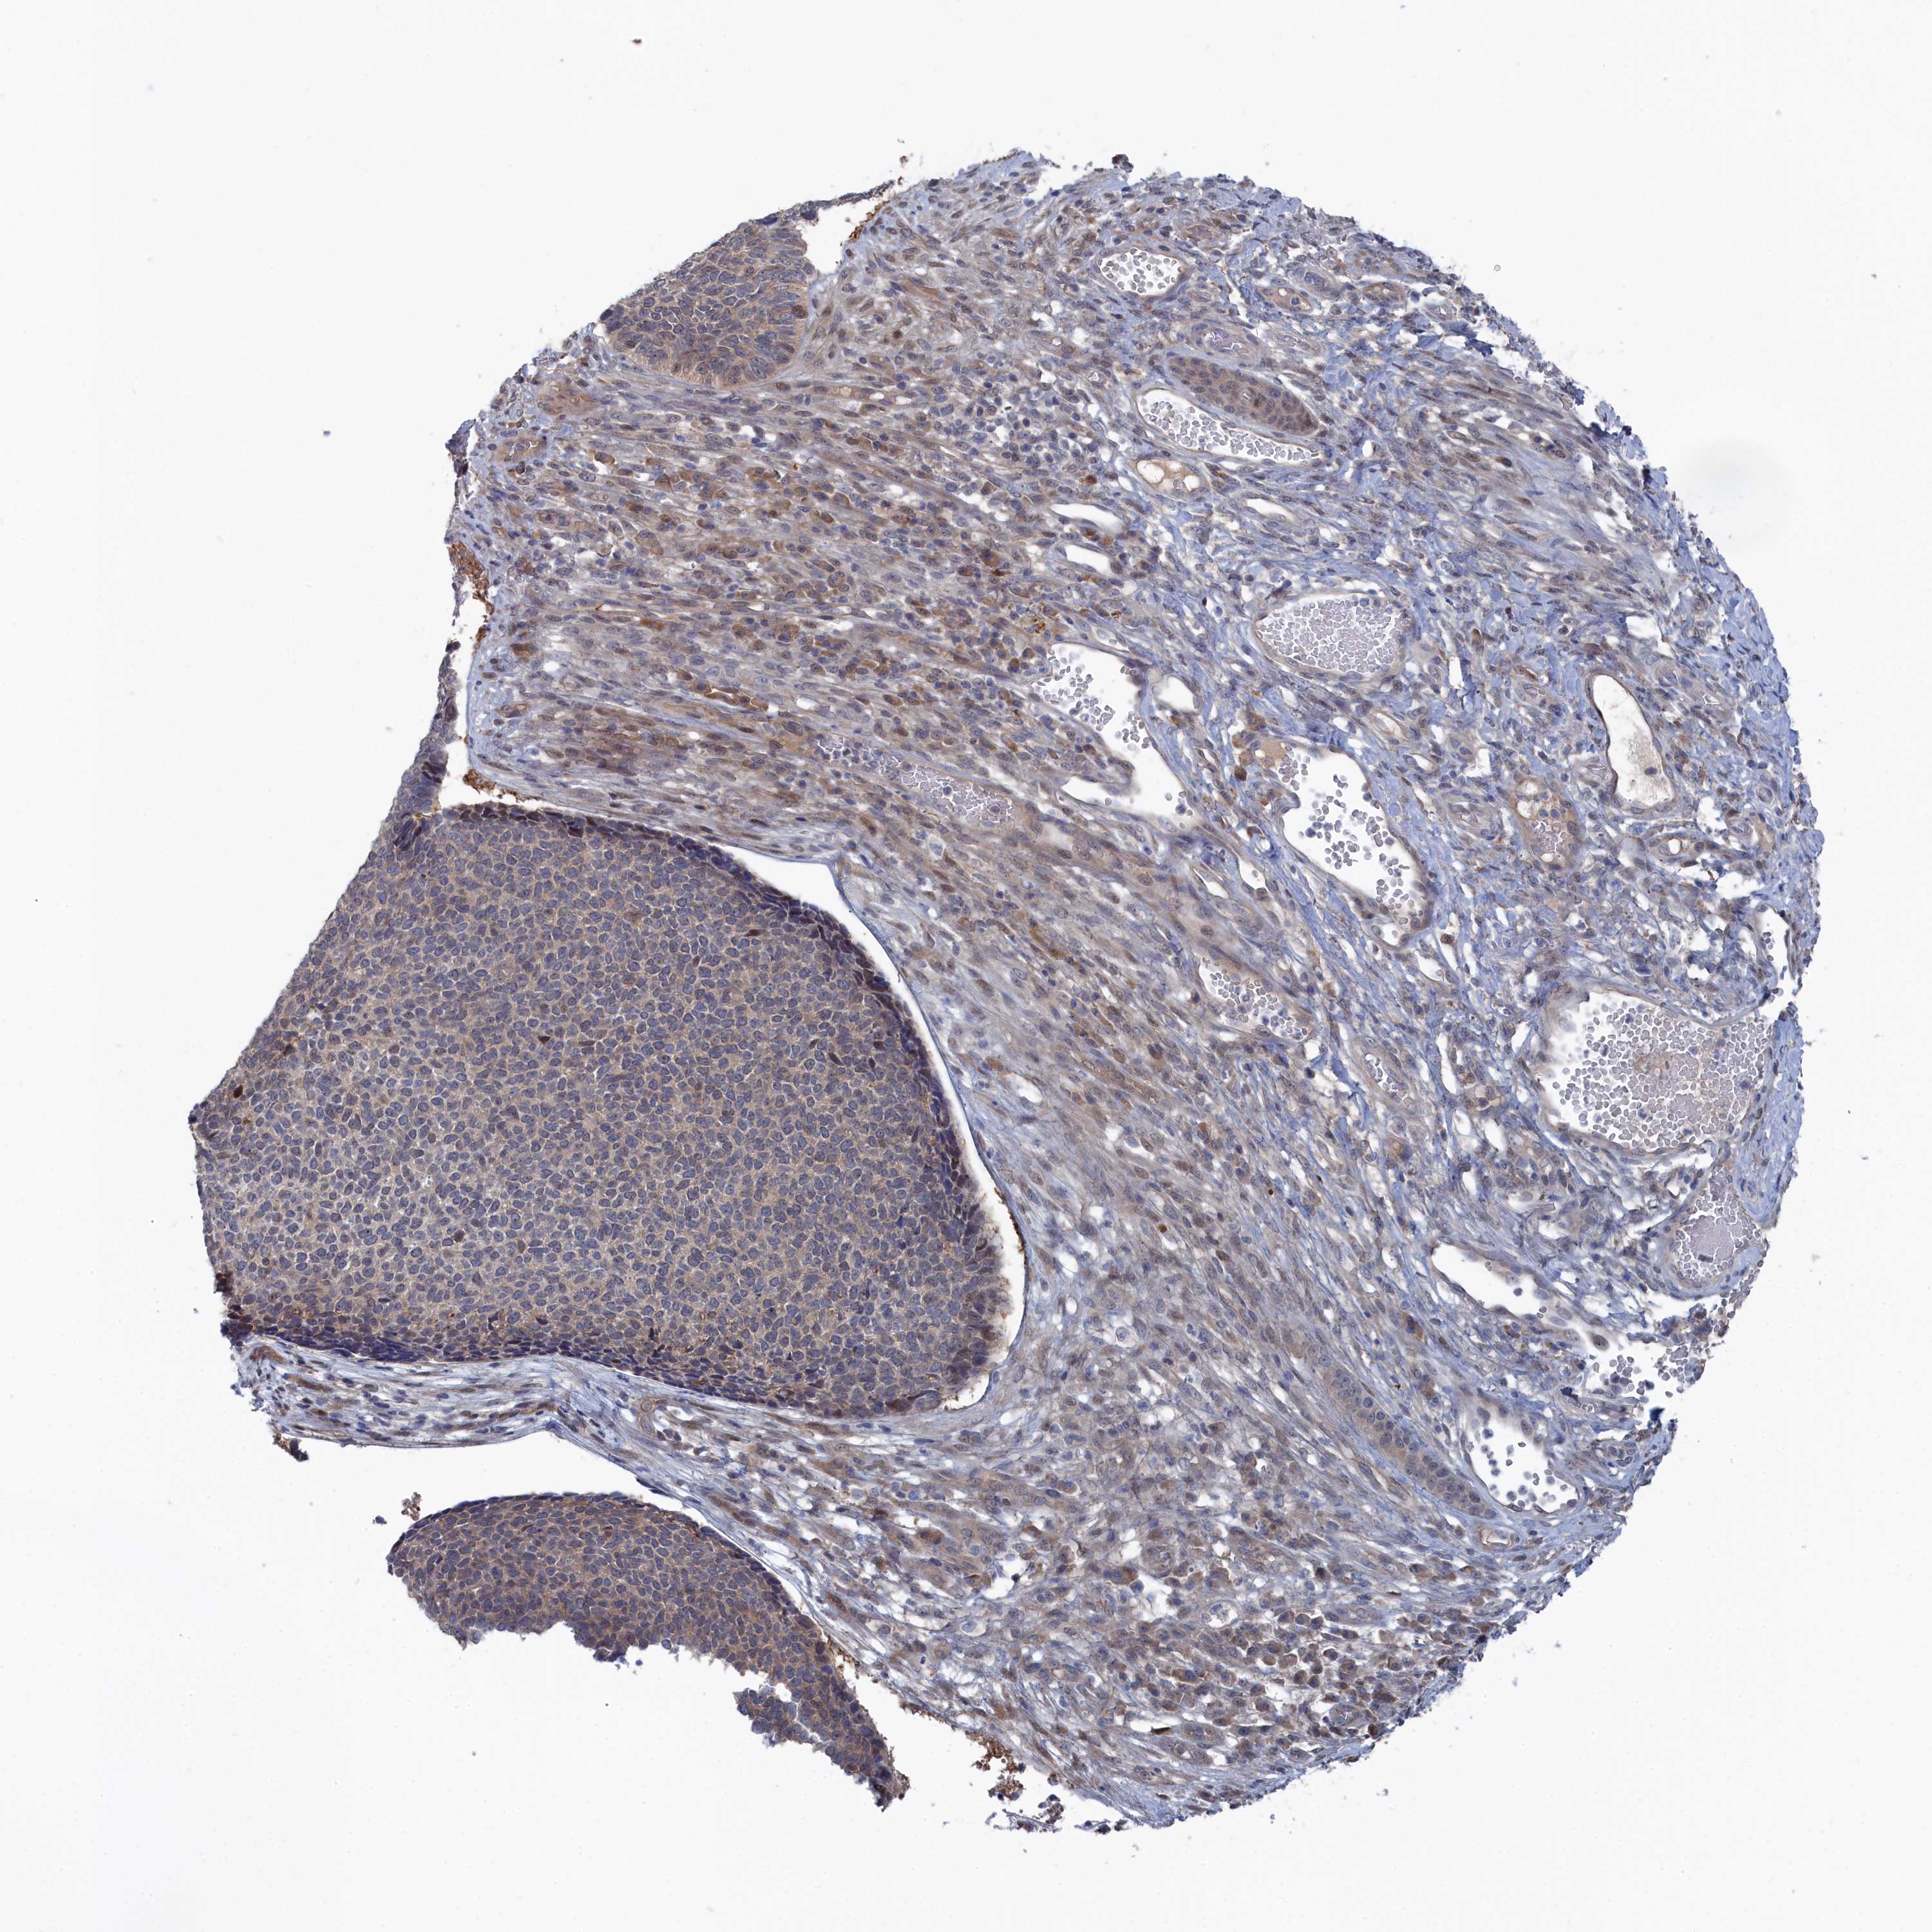

SKIN CANCER - Protein expressioni

A mouse-over function shows sample information and annotation data. Click on an image to view it in a full screen mode. Samples can be filtered based on level of antibody staining by selecting one or several of the following categories: high, medium, low and not detected. The assay and annotation is described here.

Antibody stainingi

Antibody staining in the annotated cell types in the current human tissue is reported as not detected, low, medium, or high, based on conventional immunohistochemistry profiling in selected tissues. This score is based on the combination of the staining intensity and fraction of stained cells.

Each image is clickable and will lead to virtual microscopy that enables deeper exploration of all samples and also displays staining intensity scores, fraction scores and subcellular localization as well as patient and tissue information for each sample.

Antibody HPA043254

Squamous cell carcinoma, NOS

Squamous cell carcinoma, metastatic, NOS